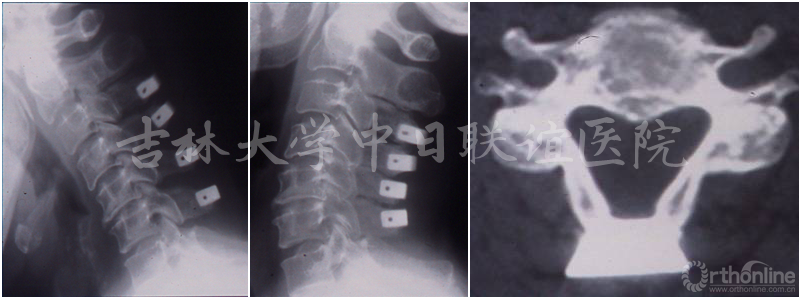

男性患者,诊断为“发育性椎管狭窄伴无骨折脱位型颈脊髓损伤”,行C3-6后路双开门椎管扩大成形术。

患者术前术后影像学资料